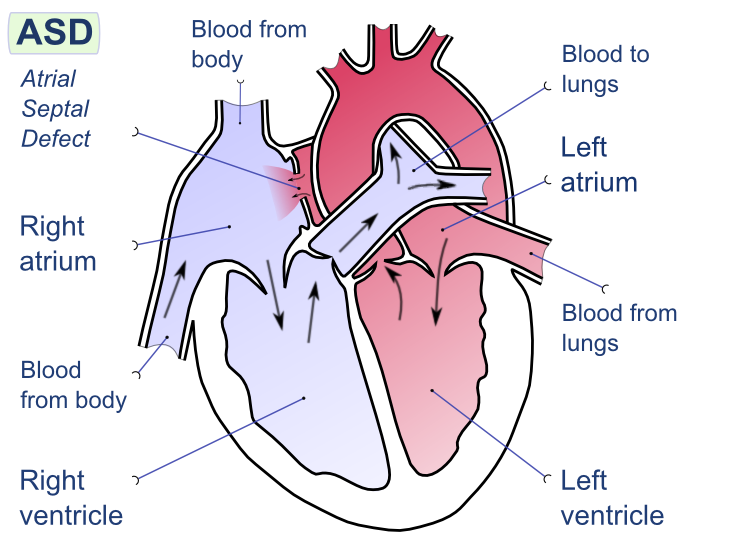

Atrial Septal Defect (ASD)

An atrial septal defect (ASD) is a hole in the wall that separates the right and left atria.

Ostium secundum is the most prevalent (90 percent of cases) cause of atrial septal defect (ASD).

Down syndrome is linked to the osteoid primum type of atrial septal defect (ASD).

An atrial septal defect (ASD) results in a divided S2 and a left-to-right shunt on auscultation (increased blood in right heart delays closure of pulmonary valve).

Paradoxical emboli are potential complications of atrial septal defects (ASD).